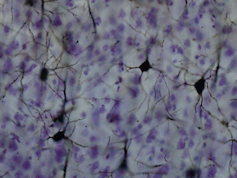

These two areas have been identified as involved in integrating emotion and memory. The claustrum is a very thin layer of neurons that are found underneath the inner neo-cortex. It is known to link to and from very many regions of this part of the brain. As such, the claustrum has been implicated in integrating stimuli from several senses and is involved in linking areas involved in emotional processing and attention.